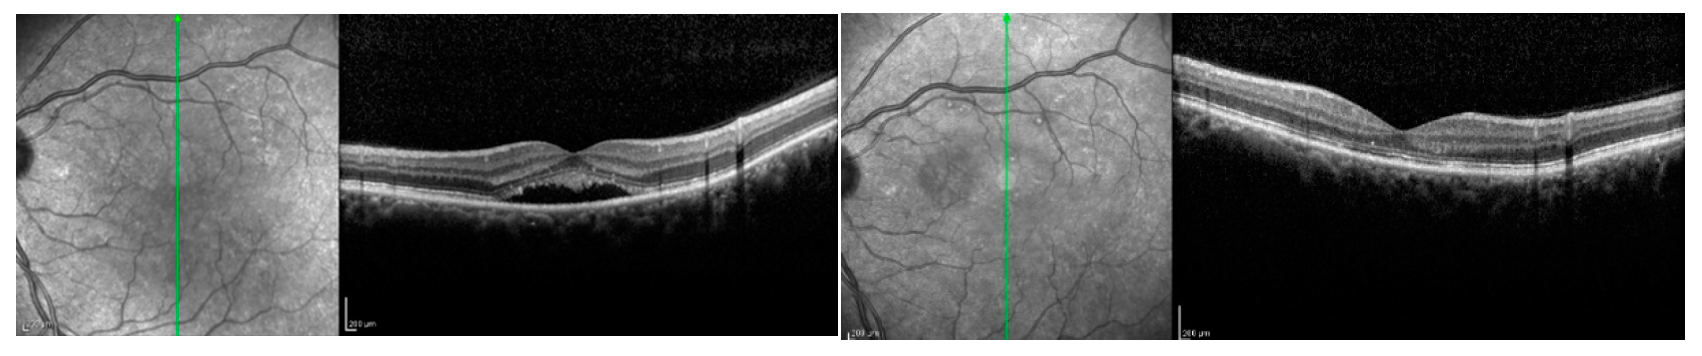

Figure 3.

Patient affected by chronic central serous chorioretinopathy treated with subthreshold laser treatment. (Left) Optical coherence tomography scan thorough the fovea (green arrow) disclosing a subretinal fluid with photoreceptors elongation before the treatment (visual acuity 20/63). (Right) Optical coherence tomography scan of the patient after subthreshold laser application, revealing the complete resolution of the subretinal fluid, with no visible laser scar (visual acuity 20/20).